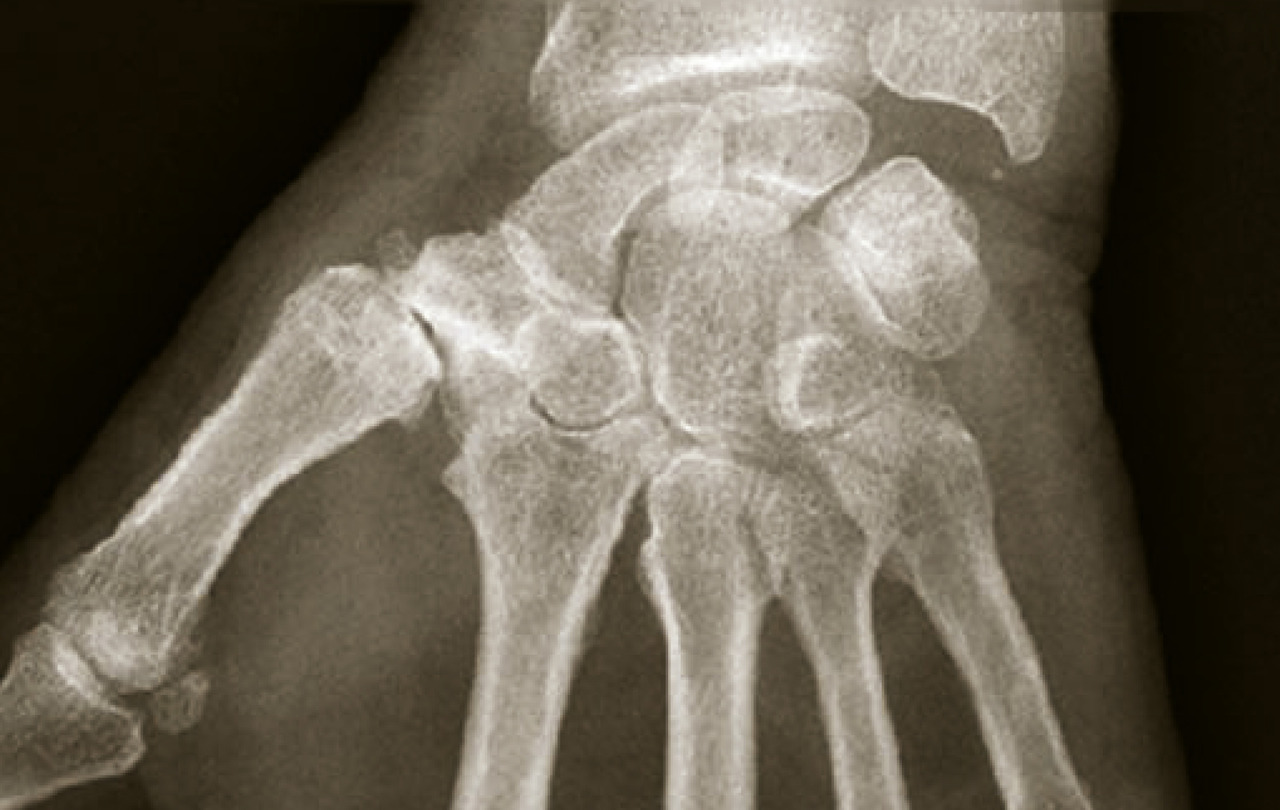

Les radiographies sont inutiles au diagnostic. Quand elles sont effectuées, elles mettent en évidence un pincement des interlignes articulaires et une ostéophytose souvent exubérante correspondant cliniquement aux nodosités décrites précédemment (fig. 7). Pour la rhizarthrose (fig. 8), l’atteinte de cette articulation précède celle de la scapho-trapézienne.